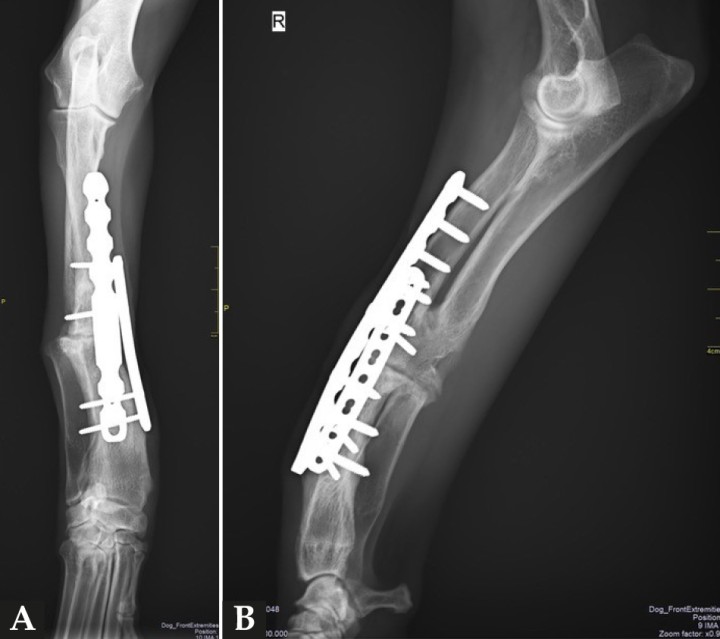

Después de la cirugía se analizaron las radiografías postoperatorias, realizándose las mismas mediciones que en la planificación, y observándose cómo los valores obtenidos tras la cirugía se correspondían con los valores planificados (Fig. 5). Se colocó un vendaje postoperatorio sencillo durante 14 días, para evitar la manipulación del área quirúrgica por parte de la paciente, lo que facilitó una cicatrización correcta de la herida y una buena recuperación del animal, que comenzó a caminar con normalidad a los pocos días de la intervención (Fig. 6).

Proyecciones radiográficas craneocaudal y mediolateral posquirúrgicas. Las radiografías muestran el resultado tras la cirugía.

Proyecciones radiográficas (A) craneocaudal y (B) mediolateral a los 4 meses de la cirugía. Las imágenes muestran la avanzada consolidación de la ostectomía.